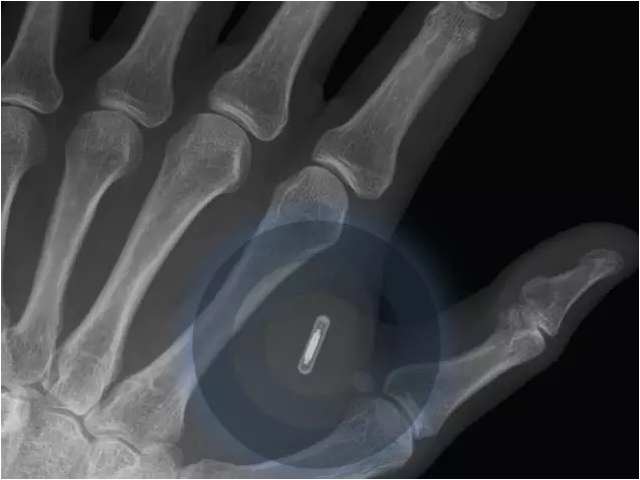

6.2025年,首款植入式手机将商业化。

2023年,依附于手机将会是一个全新的概念。报告称,约80%的受访者认为在七年内,第一部植入式手机将会商业应用。该设备能更准确追踪个人健康状况,也能通过脑电波或信号来与人进行思想交流。植入式医疗设备,例如心脏起搏器和植入式耳蜗等已成为主流。2025年内之前我们将会看到更多植入式设备的广泛应用。